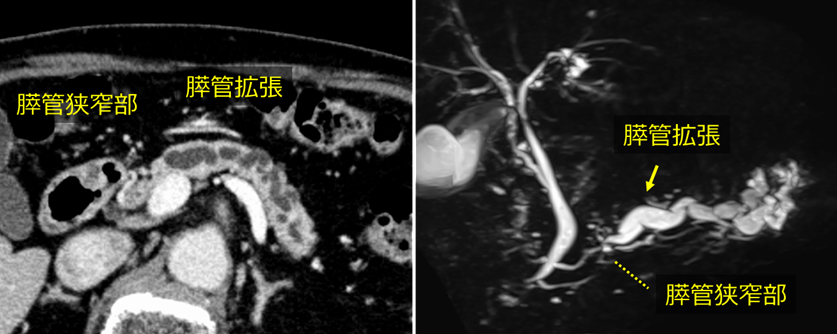

検診の腹部超音波検査で膵管拡張を指摘され、精査目的に当院を受診されました。 当院で施行した造影CT検査およびMRI検査では明らかな腫瘍は指摘できませんでしたが、主膵管の拡張が認められました。

まず、ERPを施行したところ、主膵管の狭窄を認めたため(左図)、膵管ドレナージチューブ(右図、Endoscopic Nasopancreatic Drainage:ENPD)を留置し、連続膵液細胞診(Serial Pancreatic Juice Aspiration Cytologic Examination:SPACE)を行いました。しかし結果は class 3(良性とも悪性とも断定できない結果) で、明らかな悪性所見は認められませんでした。

ERP所見

左:副膵管から造影すると、膵管の一部が狭窄していました。

右:経鼻膵管ドレナージチューブを留置し、複数回の膵液細胞診を行いました。